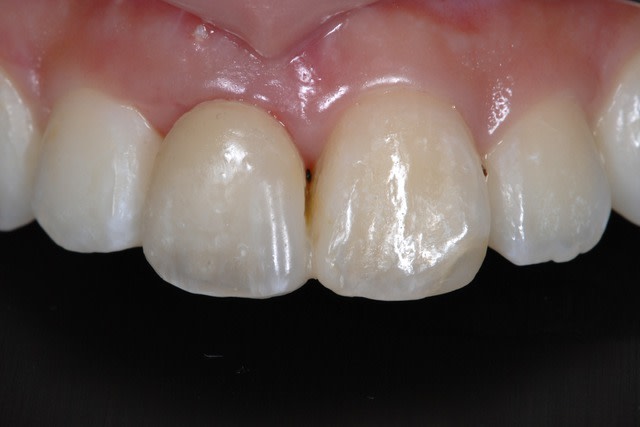

Patient vient au cabinet car son dentiste lui a enlevé sa sa couronne /Ic et la racine par la meme occasion .

-Bridge collé de temporisation .

Le patient est ok pour l'implantologie.

-Classe II div 1 .

-De l'os à souhait ,je poste les scans bientot.

-Un biotype épais .

-Un peu de perte en vestibulaire .

-Mise en esthétique immédiate ou Implant en 2 temps chirurgical avec technique du rouleau pour gagner en conjonctif ultérieurement .